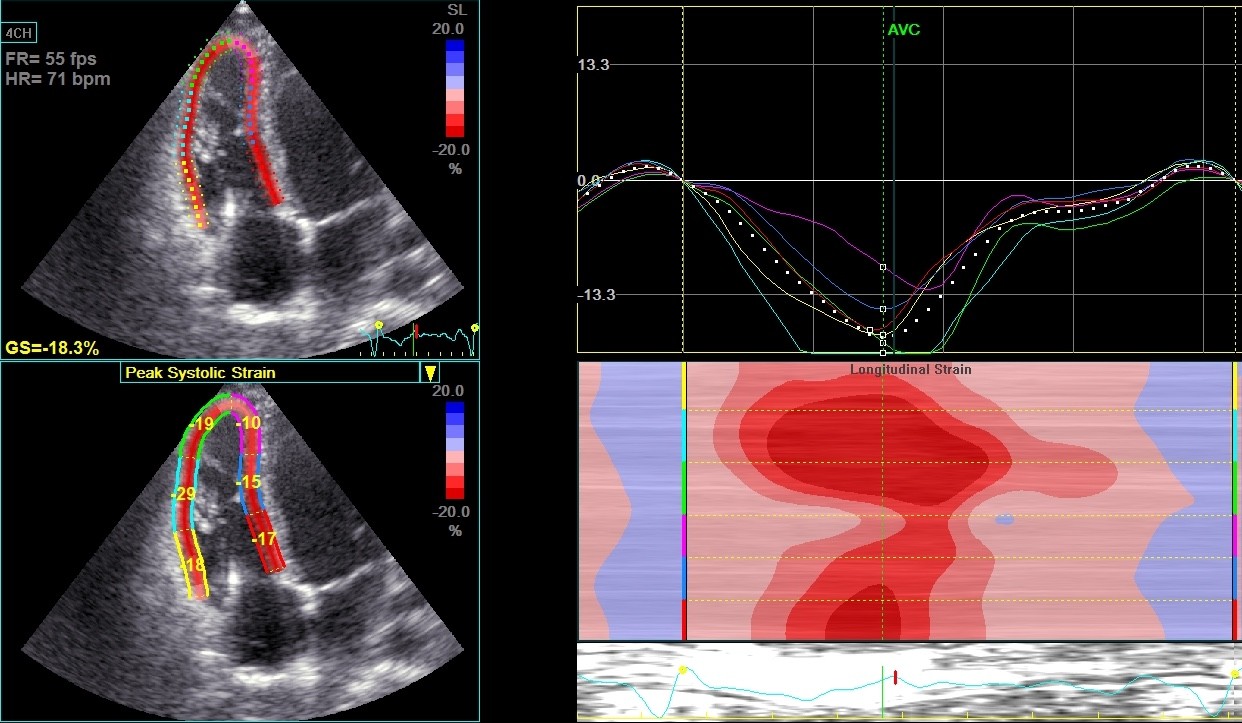

• Cut-off for RV GS -18% — signs of structural tissue change (fibrosis, fatty replacement)

Apical A-Dyskinesia & beginning aneurysm with a reduction of the FWS & GS (FWS >-23%)

Beginning disease – Early stage ACM, RV borderline in size, possible apical aneurysm, FWS & GS reduced, in MRI fatty tissue replacement